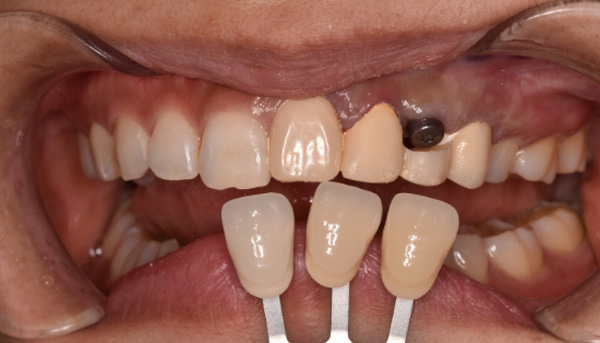

【50代女性】前歯のインプラント症例

「前歯は第一印象に関わるので失敗したくない」

治療中

治療後

津田先生からのコメント

前歯のインプラントで特に審美的に要求の高い患者様でしたので、当院で最も信頼性の高いインプラント治療プランをご選択いただきました。

| 主訴 | 抜けたままで放置していた前歯をインプラントにして綺麗にしたい。 |

|---|---|

| 治療期間 | 約4ヶ月 |

| 治療費 | 1本あたり550,000円(税別) |

| 治療内容 | 前歯のインプラント治療 |

| 治療のリスク | 前歯のインプラント治療では、審美性の問題や骨密度不足によるインプラントの不安定、神経損傷や感染のリスクがあり、術後の腫れや痛みも発生する可能性があります。 |